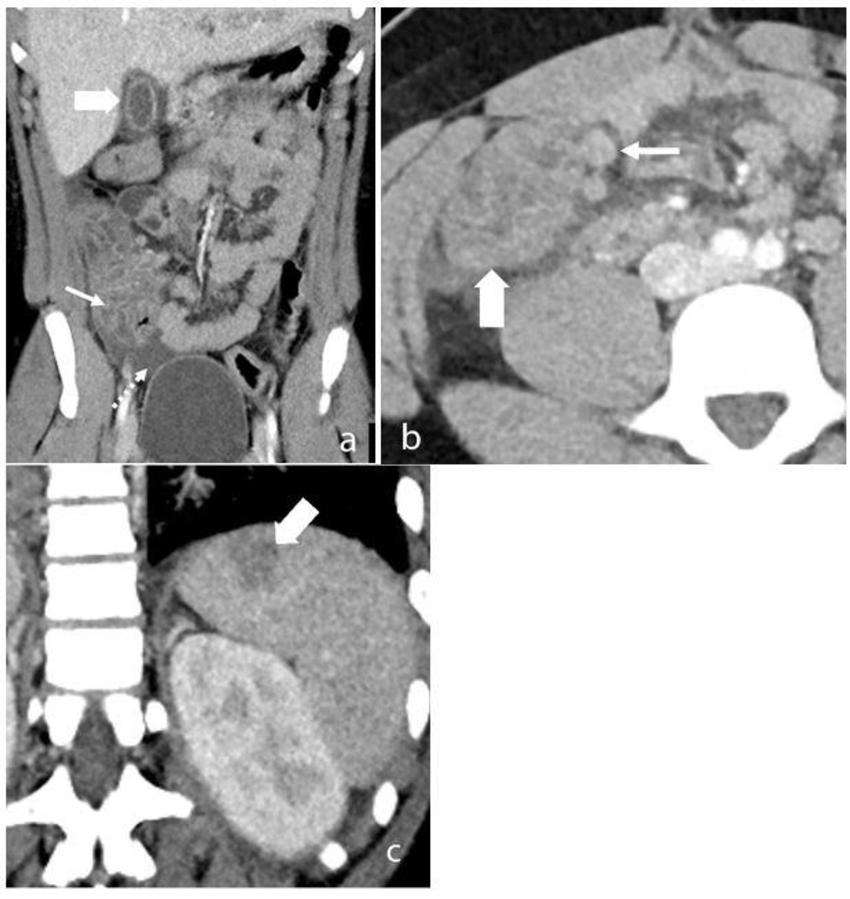

Figure 7. Contrast enhanced CT abdomen and pelvis of a 15-year-old male who presented with sepsis. (a) Coronal image of the abdomen demonstrates gallbladder wall edema (wide arrow). There is extensive thickening of the cecal wall thickening (thin arrow) and free-fluid within the pelvis (dotted arrow). (b) Axial slice through the lower abdomen showing the cecal wall thickening (wide arrow) with multiple adjacent mesenteric nodes (thin arrow) and surrounding fat-stranding. (c) Coronal image through the left upper quadrant shows a focal subcapsular, hypoattenuating region within the spleen in keeping with a splenic infarct (arrow).

High-res (TIF) version